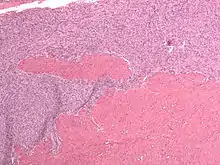

Anatomopathologie d'un sarcome stromal de l'endomètre

Microscopie

- Cellules identiques à celles du chorion endométrial à la phase proliférative.

- Moins de 10 mitoses /10 champs au fort grossissement mais parfois plus nombreuses.

- Présence de vaisseaux nombreux, à paroi épaisse et scléro-hyaline (en).

- Envahissement massif du myomètre avec emboles tumoraux lymphatiques et vasculaires possible.[réf. souhaitée]